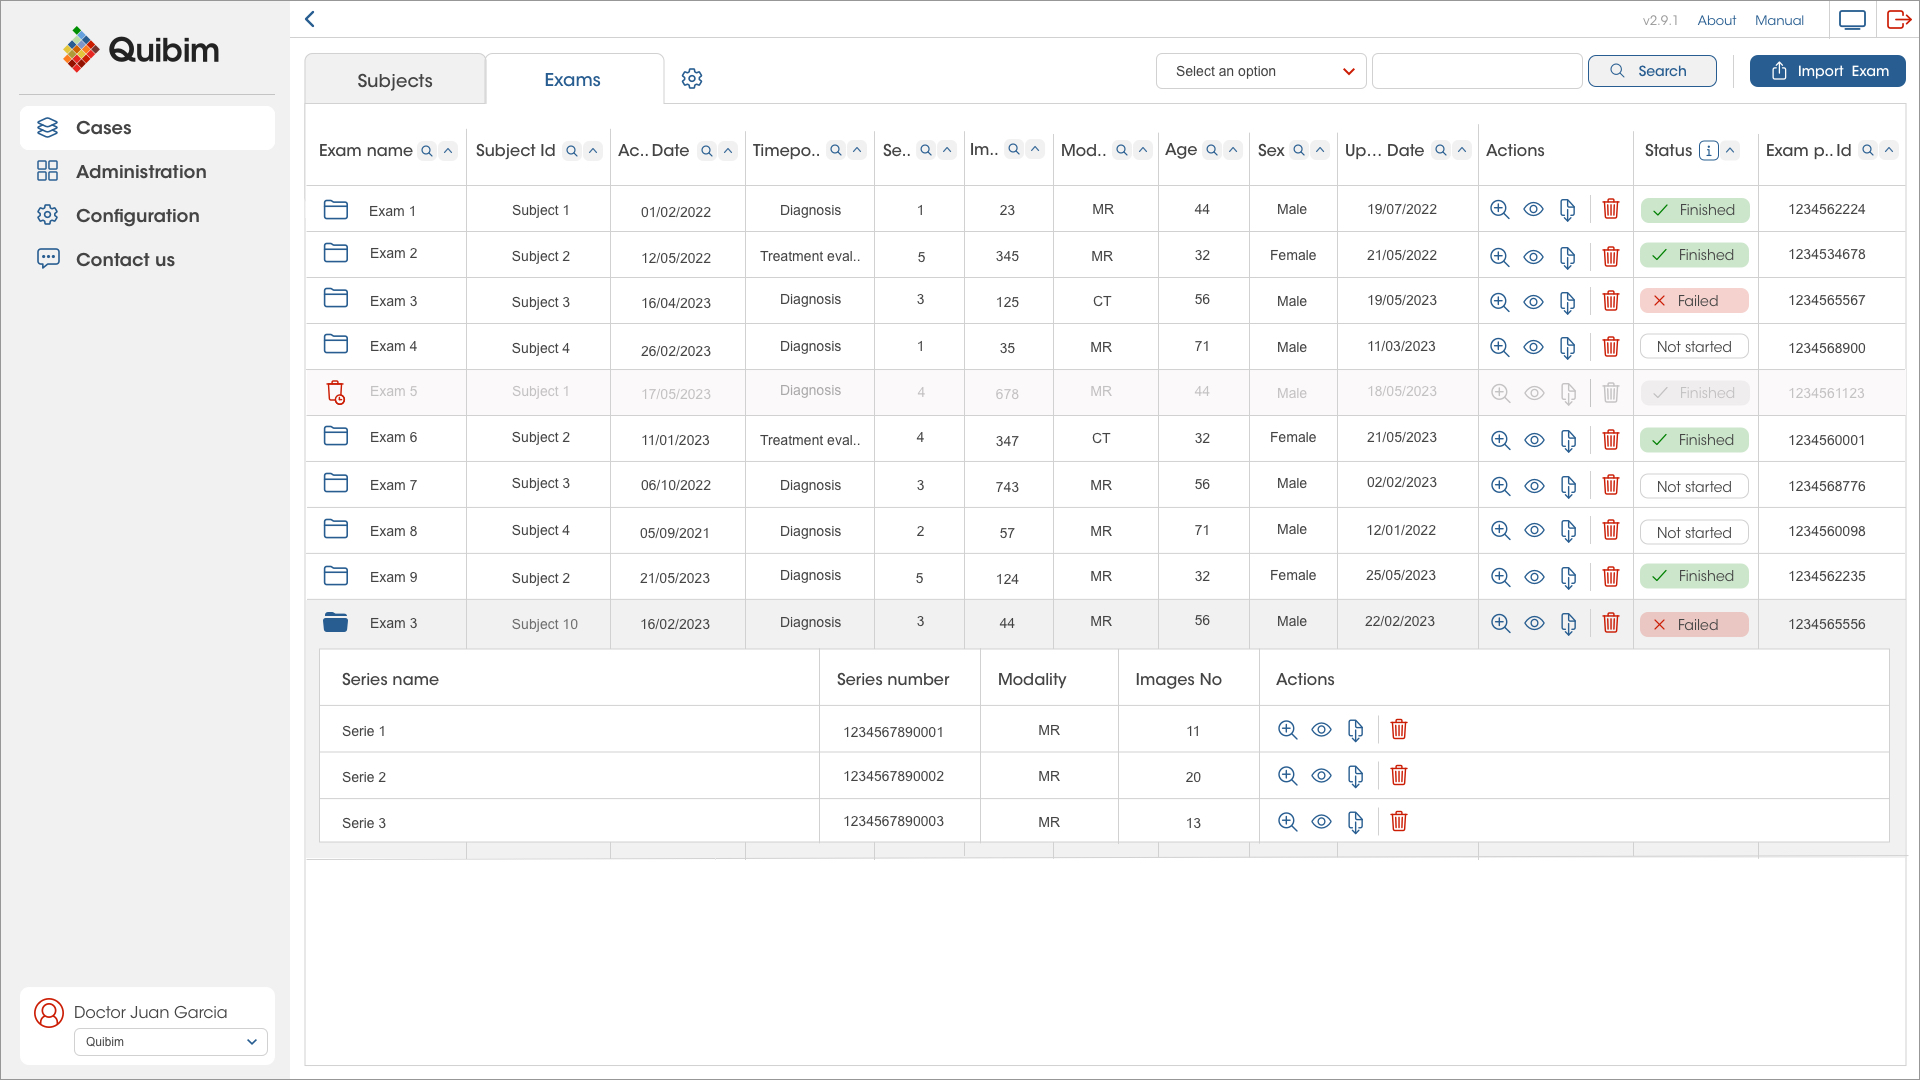

Streamlining RECIST Evaluation with AI

Designed to optimize radiology workflows, Quibim’s solution—integrated within the QP-Insights platform—leverages advanced deep learning algorithms to accelerate tumor response evaluation based on RECIST 1.1 criteria.

AI-driven tools are seamlessly embedded into the workflow to automatically detect, segment, measure, and track lesions in the lungs and liver. The algorithm is capable of identifying new lesions and monitoring existing ones across follow-up timepoints following the baseline scan.

Radiologists retain full control over the evaluation process, with the ability to manually adjust the AI-generated measurements and add lesions from other anatomical regions in an intuitive and user-friendly interface.

All data is automatically stored in a standardized digital format within the platform, enabling automated RECIST 1.1 response calculations and generating a final summary report of the complete assessment.

The Multi-Omics Data Management Solution

QP-Insights platform is highly customizable based on the user’s requirements, includes an embedded zero footprint DICOM viewer for radiological readings, semi-automatic treatment response evaluation, AI-driven organ/lesion segmentation and automatic quantification of imaging biomarkers, incorporates electronic case report forms (eCRF) interoperability and a DataMiner tool.